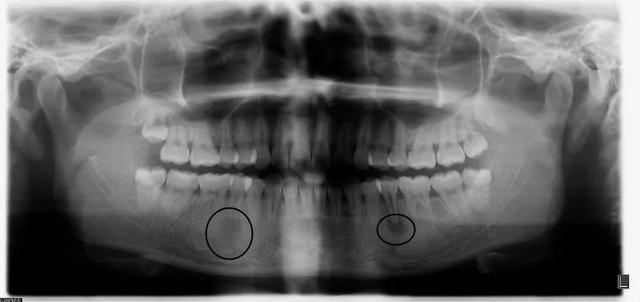

小媛术前全景片: 两侧下前磨牙根尖大面积暗影

考虑到根尖孔未闭合,呈喇叭口状

建议拟行根尖屏障术